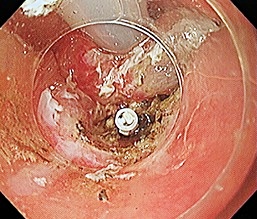

[咽頭腔外魚骨異物] 手術:内視鏡的粘膜下層剥離術(異物除去)

内視鏡画像